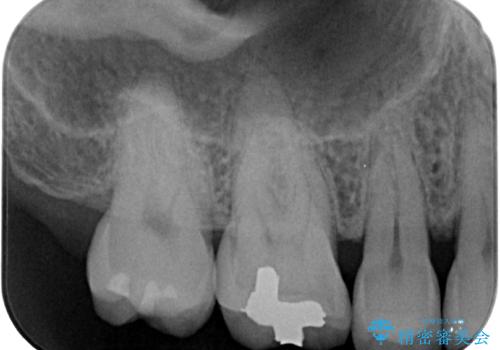

- 舌で触ると段差が気になるとのことで来院された患者様です。歯質がわずかに欠けており金属の詰め物の間に小さなギャップが生じていました。

咬み合わせも強い方なので物性、適合性に優れたゴールドインレーにて治療をしていくことになりました。

拡大鏡視野下で金属の詰め物、虫歯を除去し、ゴールドインレーに適した形に整えました。